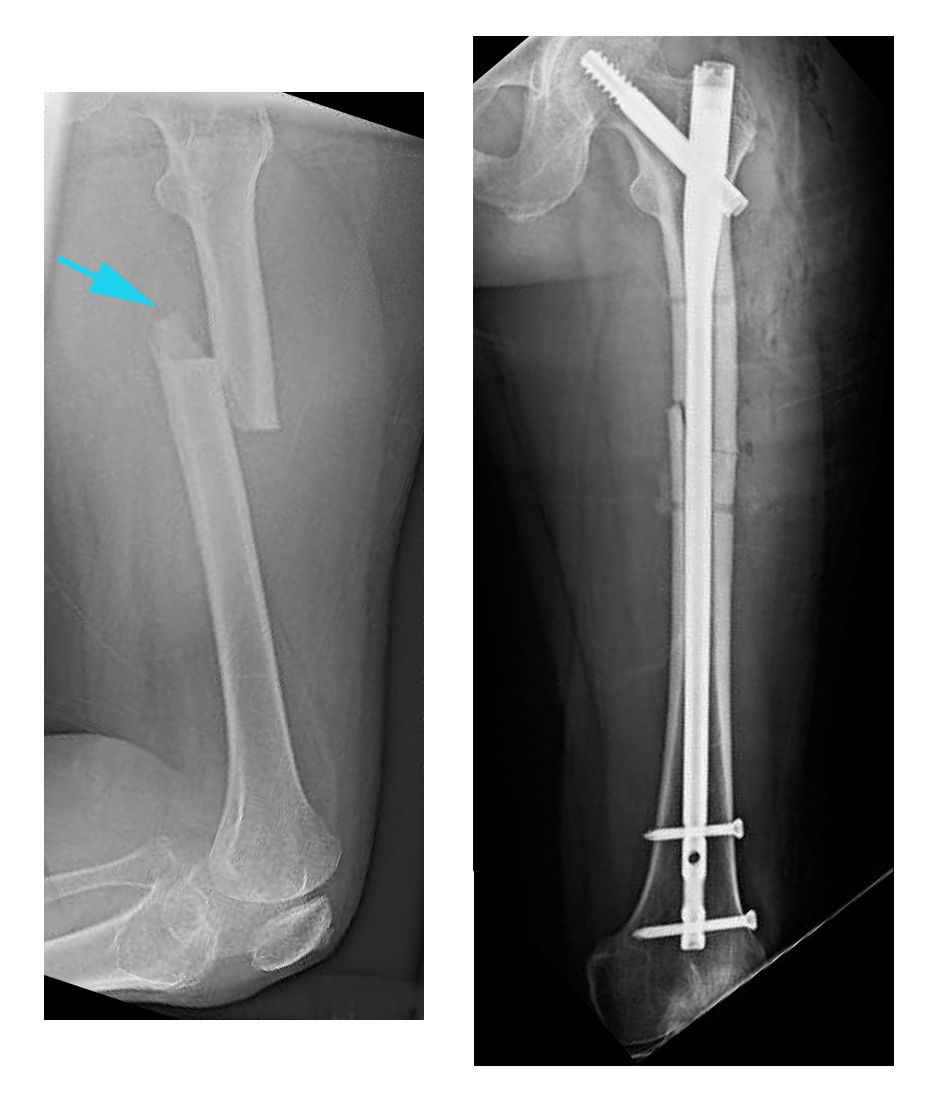

Una radiografía muestra una fractura transversal del fémur. La ruptura se produce en una línea recta horizontal que atraviesa la diáfisis.

Reproducido desde JF Sarwak (ed): Essentials of Musculoskeletal Care, ed 4. Rosemont, IL. American Academy of Orthopaedic Surgeons, 2010

(Izquierda) Esta radiografía, tomada de perfil, muestra una fractura transversal del fémur. (Derecha) En esta radiografía frontal, la fractura se trató con clavos intramedulares.